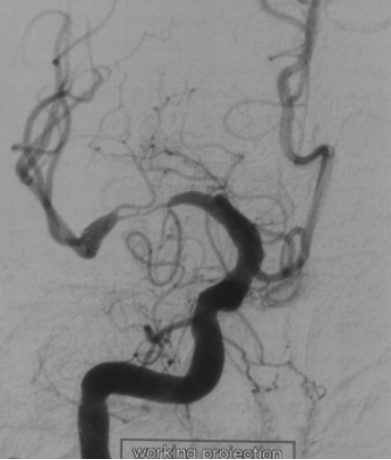

血管造影显示右侧MCA重度狭窄,近端血管直径3mm,紧邻狭窄远端 2.8mm,远端近分叉部直径3.8mm

在放大的血管造影上看,可见外侧豆纹动脉在远端紧邻狭窄部位发出

由于担心球囊扩张后的雪犁效应,影响豆纹动脉的通畅性,选择比较保守的gateway球囊 2.75*15进行扩张